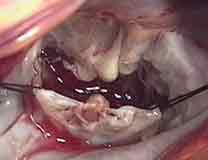

僧帽弁

僧帽弁形成術の成績は非常に良好で、僧帽弁逸脱症候群、

僧帽弁閉鎖不全症の多くの場合(95%以上)、形成術を行うことができます。

また、感染性心内膜炎による僧帽弁の逆流に対しても

積極的に自己弁を温存するように努めています。

弁の変性(または破壊)の形態によって臨機応変に手術様式を選択しますが、

主な形成方法は、悪くなっているところを切除し、周囲の組織を寄せてその部分を埋め合わせたり、

人工検索を作って弁を支えたり、パッチを用いて穴を閉鎖したりします。

最後に弁輪に「当て布」(弁輪形成)をして形成します。